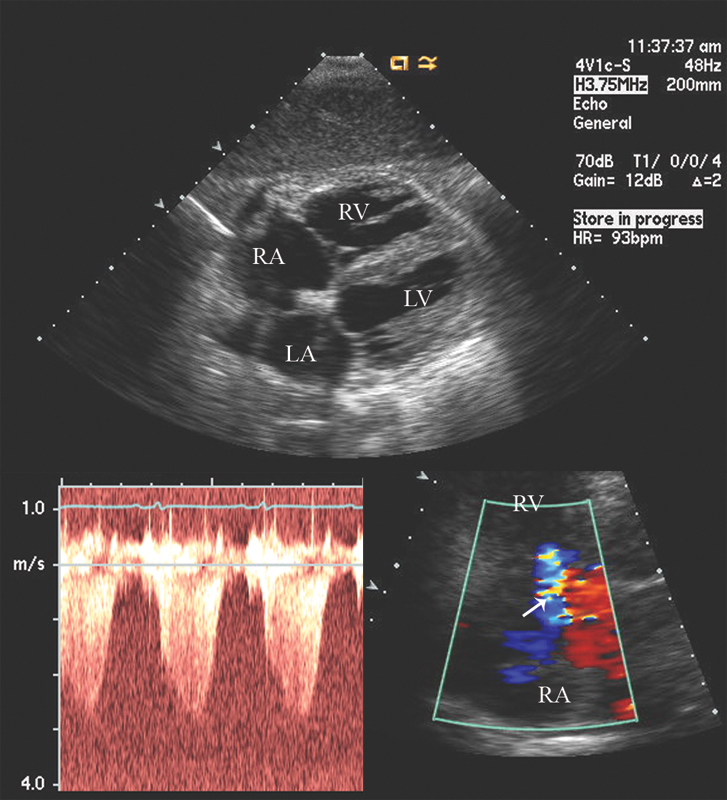

فحوصات تشخيصية لبعض امراض القلب والشرايين التاجية